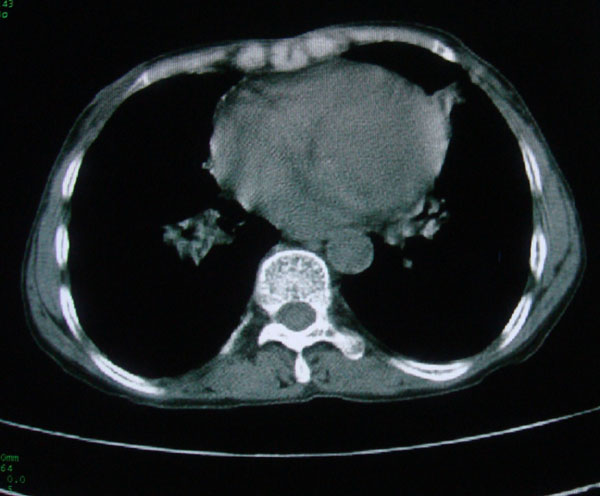

标题: CT15046:F59Y,咳嗽间断咳血丝痰就诊. [打印本页]

标题: CT15046:F59Y,咳嗽间断咳血丝痰就诊.

咳嗽\间断咳血丝痰就诊.

考虑支气管扩张并感染

1慢支伴感染;右下肺周围型肺癌。

本例应该是“慢性疾病并发多种合并症”即:慢支并感染并支气管扩张征!结合病灶分布 形态分析,不除外合并“继发性肺结核”!

慢性支气管炎伴全小型肺气肿、支气管扩张、感染、间质纤维化。

多考虑支气管扩张并感染,双下肺继发性肺结核不除外